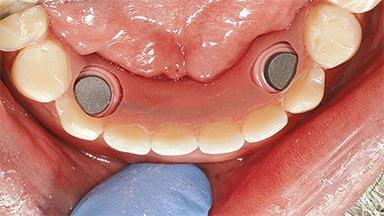

An 83-year-old man presented together with his caregiver at the dental department of the Medical University of Innsbruck, Austria with complaints of swelling in the right maxillary canine area and loss of retention of his 5-years-old mandibular denture. The patient had a significant medical history (20 years) of bipolar affective disorder with moderate depression (F 31.3) and dementia in Alzheimer’s disease (F 00.2). The patient had been in ambulant psychiatric therapy for his depressive illness for the past 20 years. He lived alone and had no children; his sister assisted with daily living. She reported that the patient exhibited compulsive hoarding behavior. In the previous two months, she had noted increasing disorientation and vertigo in the patient. She therefore accompanied him for a medical consultation at the Department of Psychiatry and Psychotherapy of the Medical University of Innsbruck. He was released home after a 6-week inpatient stay.

# of Implants 2

Type of Implants One-Piece

Attachment One-Piece

Defining Characteristics Fully edentulous lower jaw to be rehabilitated with an implant-borne removable overdenture